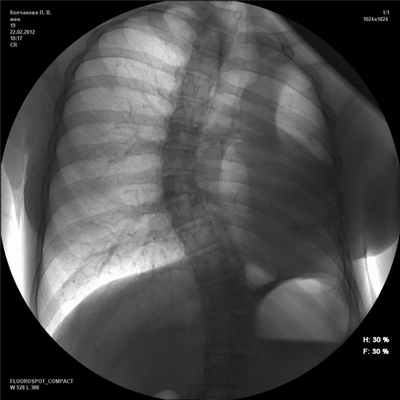

При поступлении общее состояние больной относительно удовлетворительное. Подкожный жировой слой плохо развит. Аускультативно справа выслушивалось жесткое дыхание, хрипов не было. Тоны сердца ясные и ритмичные. Пульс 75 в 1 мин, удовлетворительного наполнения и напряжения. АД 110/70 мм рт.ст. Язык чистый. Живот мягкий, безболезненный. При полипозиционной рентгеноскопии и рентгенографии органов грудной клетки левая половина грудной клетки деформирована и затемнена (рис. 1). Рисунок 1. Рентгенограмма грудной клетки в прямой проекции. Смещение органов средостения влево, легочная грыжа, искривление позвоночника. Отсутствие левого легкого после пневмонэктомии. Тень средостения определялась слева от средней линии. Правое легочное поле было прозрачное, без очаговых и инфильтративных теней. В переднем средостении определялась легочная грыжа. При приеме водорастворимого контрастного вещества в положении больной на правом боку отмечался заброс препарата в трахею на уровне ключиц. Диаметр свищевого хода 5 мм.